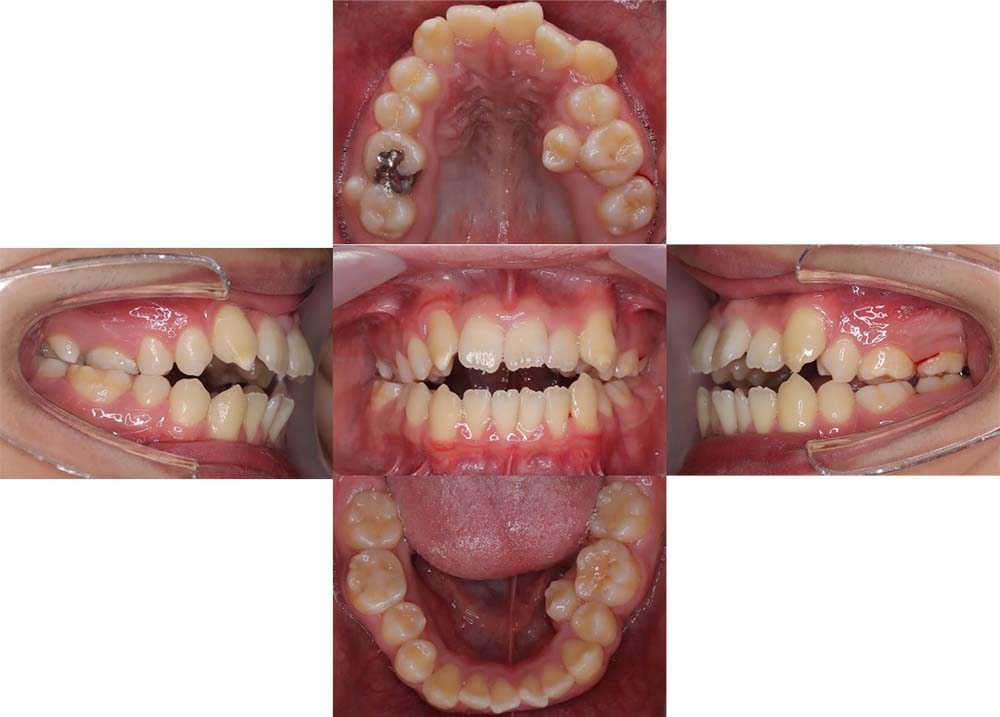

症例03

| 主訴 | 歯並びがガタガタしている。 |

| 診断名あるいは主な症状 | 過蓋咬合、叢生 |

| 年齢/性別 | 26歳・女性 |

| 矯正ステージ | 大人の矯正治療 |

| 治療方法 |

ワイヤー矯正 歯科矯正用アンカースクリュー(3本) |

| 抜歯部位/抜歯有無 | 抜歯 |

| 治療内容 | 上下顎の奥歯を後方に移動後、ガタガタの改善と上下顎前歯を後退させた。 |

| 費用 |

90万円程度(2025.10時点の料金となります。) ※矯正基本料金、アンカースクリュー、審美ブラケットを含む |

| 治療期間 | 2年8ヶ月 |

| 主なリスク・副作用 | 痛み、歯根吸収、歯肉退縮、虫歯、後戻り |